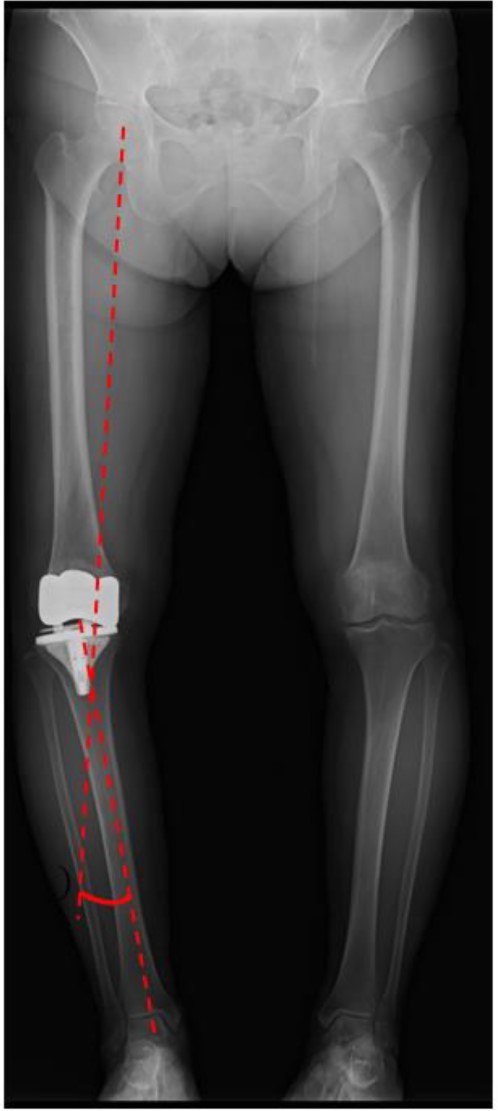

A preoperative standing anteroposterior plain radiograph of the right knee showed a hip-knee-ankle angle of 14 varus alignment (Fig. 1). Preoperative lateral plain radiographs showed posterior subluxation of the femoral component at 10 years after surgery (Fig. 2). Preoperative varus and valgus stability of the knee joint in extension were assessed with stress radiography using a Telos arthrometer (Telos SD 900 Stress Device; Telos Medical Co., Ltd, USA). The patient was instructed to lie supine on a table for the measurement. During varus and valgus stress testing, a force of 150 N was applied just above the joint on the lateral or medial femoral condyle to test for varus or valgus instability (Fig. 3) [8]. Cross-sectional anteroposterior imaging using Tomosynthesis-Shimadzu metal artifact reduction technology (T-smart) (Japan) showed tibial component subsidence at the medial tibial plateau (Fig. 4).

Post-operative standing plain radiograph. The hip-knee-ankle angle was 14° varus.